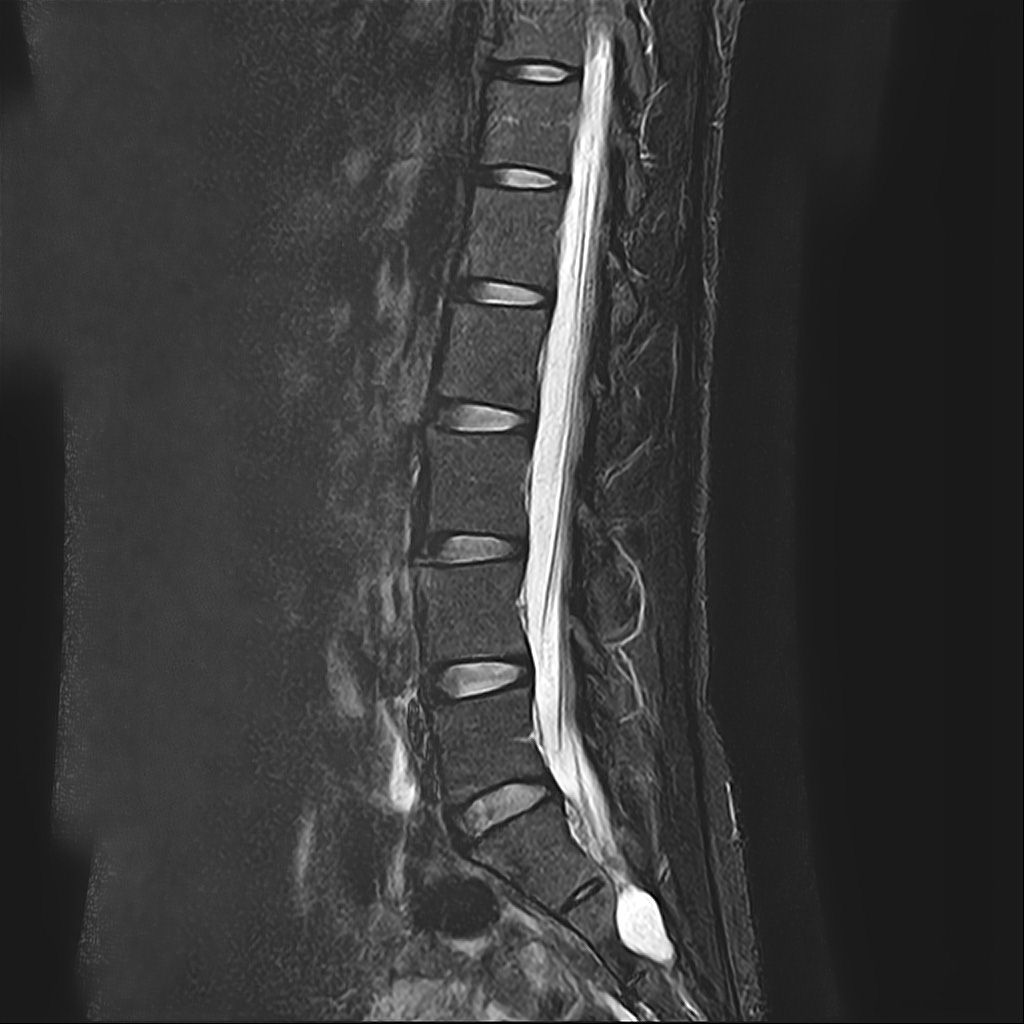

낭종s1-3번까지 꼬리뼈쪽으로 크게 나있다고했고, 단면상으로는 s2,3번이 촬영이 안되서 확인이안된다합니다. 허리디스크가 미약하게 4,5번에 있다고 했는데,

혹시 디스크로 인한 신경눌림인지, 낭종으로 인한건지 알수잇나요?